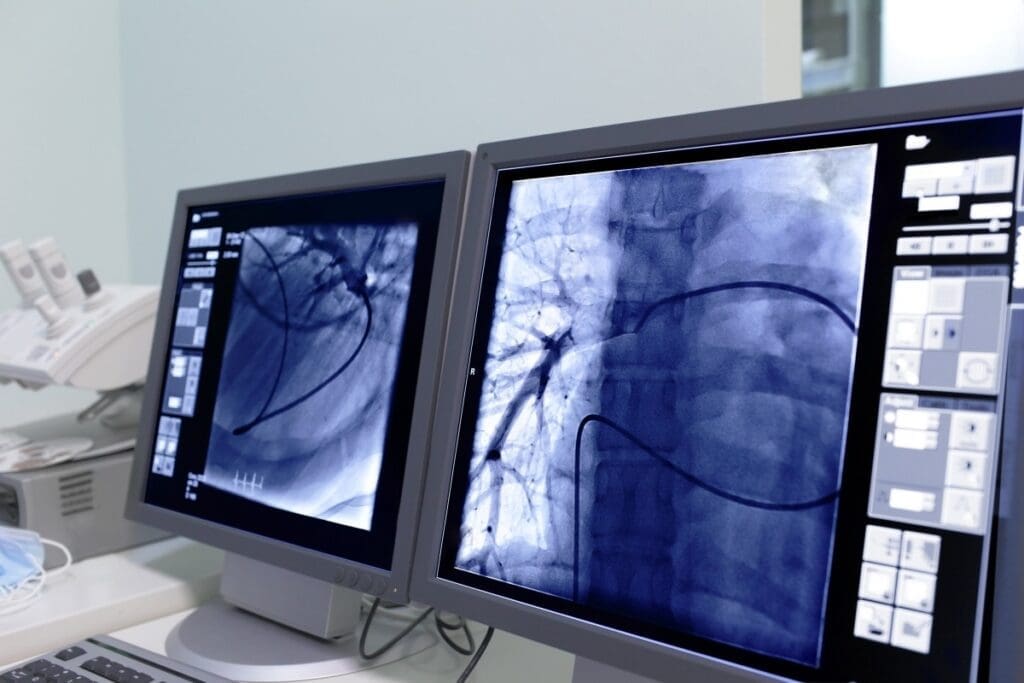

During the biopsy, a CT scan guides the insertion of a needle into the targeted area. The CT scanner shows real-time images. This lets our interventional radiologist accurately find the area and take tissue samples.

The IR Biopsy requires a needle to be inserted into a specific area. CT guidance is key, helping the radiologist place the needle accurately. This imaging lets them see the needle’s exact location in real-time.

Local anesthesia is used to make the procedure less painful. The radiologist makes a small cut in the skin. Then, the needle is guided to the right spot using CT images.